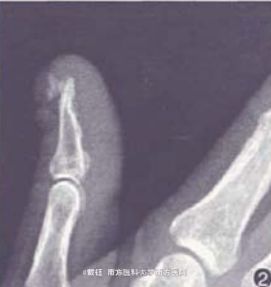

皮肤科情况:右手大拇指甲板远端缺如,近端甲板表面粗糙不平。有少许甲碎屑。拇指远端一质地坚硬、米粒大小的结节,有轻度触痛.表面平滑,无红肿、破溃和分泌物。右手X线片示:右手拇指远端背侧见一绿豆大骨性结构,呈菜花样,以宽带与拇指相连,实质密度较均匀,中央有骨小梁结构,周围软组织无肿胀以及异常密度影。

诊断:右手拇指末节远端背侧外生骨疣。转诊外科后给予手术切除治疗,现仍在随访中。

本病的x线特征为末节指指骨与远端相连的骨性高密度影,由于本病早期临床症状不典型,多表现为甲下脓肿、甲板缺失等。易误诊为嵌甲、甲下寻常疣、甲下感染或甲周纤维瘤等而延误治疗。引自《国际皮肤性病学杂志》,doi:10.3760/cma.j.issn.1673-4173.2009.01.008